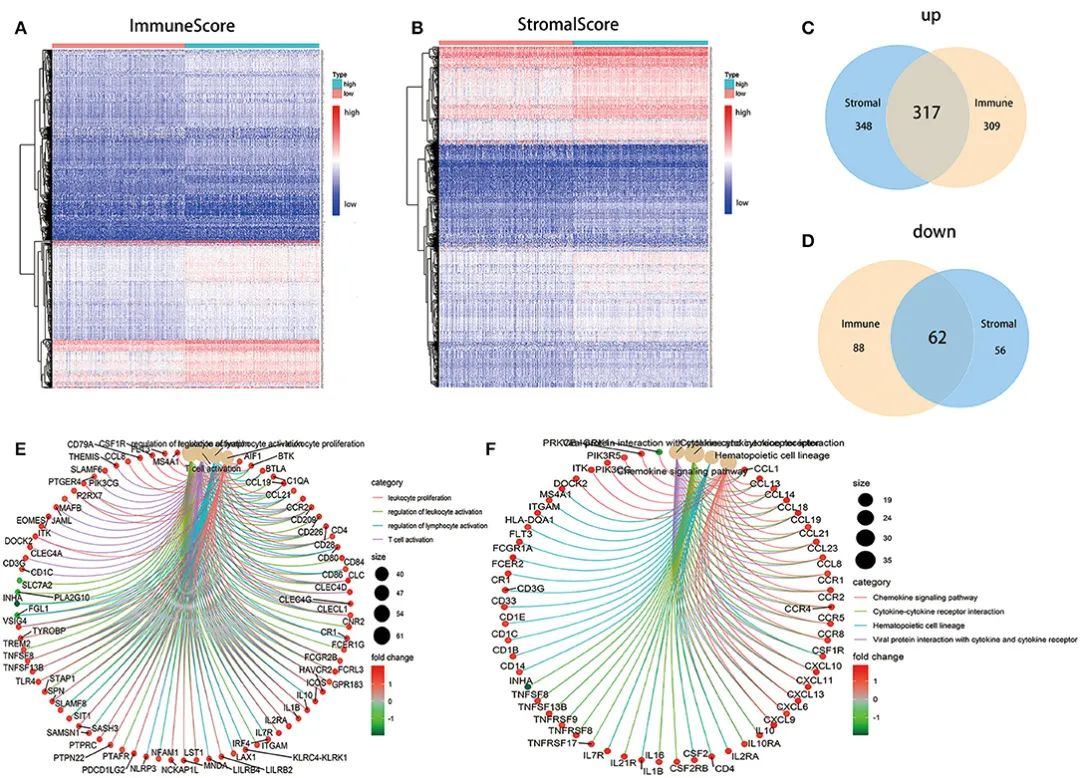

滑动查看更多 点击查看大图

期刊封面图设计

滑动查看更多 点击查看大图

论文图表排版

滑动查看更多 点击查看大图

论文图表美化

滑动查看更多 点击查看大图

数据分析与作图

滑动查看更多 点击查看大图

我们的数据分析人员全部来自清华、北大、中科院、协和、NIBS等国内顶尖研究机构,均发表过高分SCI论文,非常擅长生物、医学等领域各类型数据的分析与作图,可以完成基因组学、转录组学、蛋白质组学、代谢组学、表型组学、多组学、GEO和TCGA等数据库挖掘、临床病例数据分析、Meta分析、分子模拟与对接等各种数据分析与作图的项目。他们优秀的学术背景,保证了他们一流的分析水准。